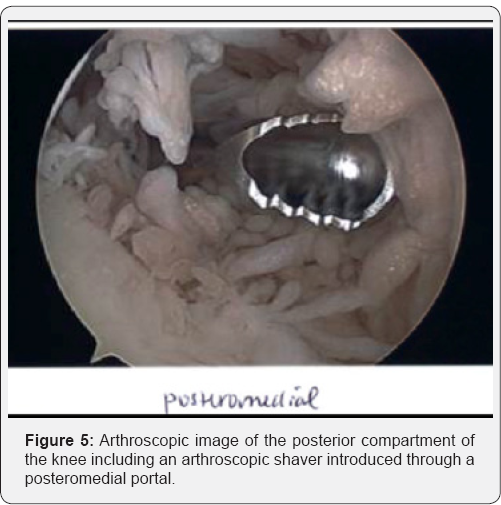

Multiple biopsies were taken from the synovial projections and the capsule itself. Complete arthroscopic synovectomy and debridement was then performed, which included using an accessory posteromedial portal for instrumentation to the posterior compartment of the knee joint (Figure 5). His postoperative recovery in the hospital was uneventful, and his Coumadin therapy was resumed. At his 3-week post-operative visit, the patient had some persistent pain and ongoing effusion, attributed to surgical hematoma. This effusion resolved slowly; unfortunately, he did suffer some recurrence of effusions. Surgical pathology from each knee showed proliferative synovia with primarily villous architecture of adipose tissue without atypia (Figure 6). A focal lymphoid reaction was present, and no pigmentation consistent with pigmented villonodular synovitis (PVNS) was found (Figures 7 & 8).